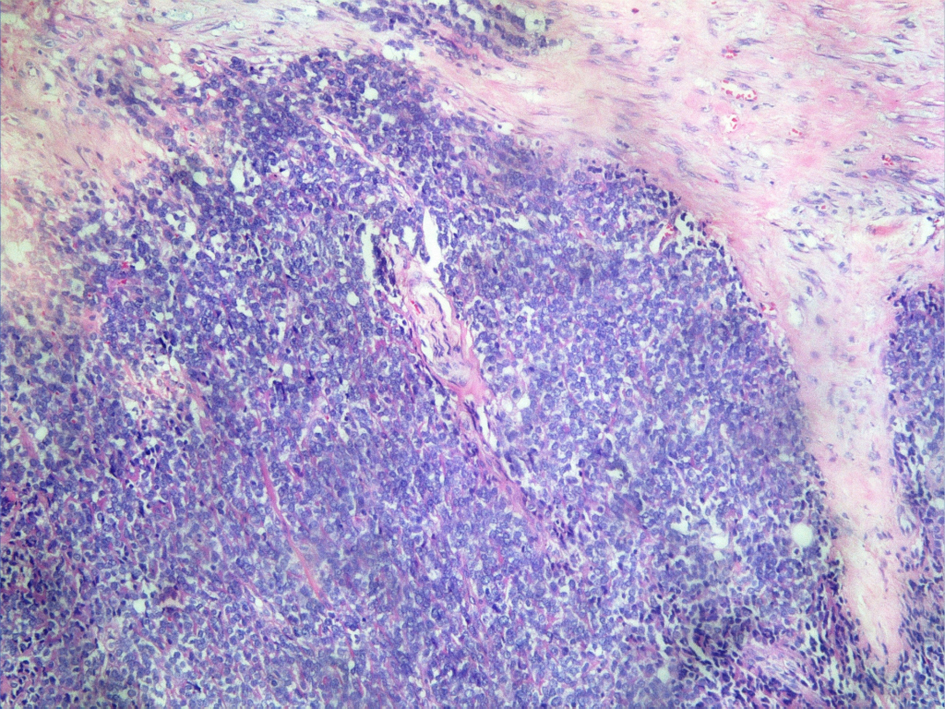

A 17-year-old girl presented with swelling at the clitorial region of few weeks duration. On examination, there was a swelling 3 × 2 × 2 cm at the clitorius. Computerized tomography (CT) scan of the abdomen and pelvis showed a right ovarian cyst of 3.5 × 2.5 cm in addition to the clitorial mass. She underwent diagnostic laparoscopy and left ovariectomy for the ovarian lesion and excision of the clitorial mass at the local hospital and was subsequently referred to us. Her performance status was 0, blood and serum chemistries were normal and lactate dehydrogenase was 405 U/L. The histopathological examination of the specimen from clitoris showed a neoplasm composed of round cells in large lobules separated by fibrocollagenous stroma, cells with scanty to moderate cytoplasm and vesicular nuclei, and many thin walled blood vessels were seen (Fig. 1). The tumor cells were strongly positive for MIC2, positive for neuron-specific enolase and negative for desmin, cytokeratin, myogenin and synaptophysin (Fig. 2). This was diagnostic of PNET/ES. The ovarian lesion was non-malignant. She was started on chemotherapy with vincristine, adriamycin, cyclophosphamide alternating with ifosphamide and etoposide and received local radiation 45 Gy/20# at ninth to 12th weeks. She achieved complete remission and chemotherapy was continued for 1 year. However, 4 months after treatment completion, she developed local recurrence in the form of well-defined mass 2 × 2 cm at the mons pubis. MRI showed multiple vulval deposits, deposits in the lower anterior pelvic wall, bilateral iliac bone, sacrum and femur (Fig. 3, 4). Bone scan showed multiple bone deposits and CT scan of chest showed multiple lung metastasis. She was given only supportive care and she died 6 months later.

![]() Click for large image | Figure 1. Round cells in large lobules separated by fibrocollagenous stroma (H&E ×20). |